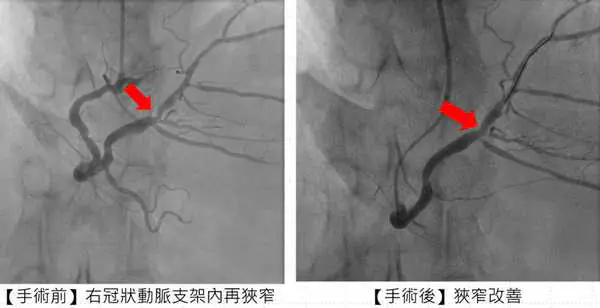

心臟科專家陳建鈞醫師說,病人有多次支架再阻塞的病史,加上長途奔波與生活壓力,病情更加複雜。經團隊縝密評估後,決定採用「刀片氣球」及「塗藥氣球」治療,既能打通血管阻塞,也可降低再度狹窄的風險,大幅縮短康復時間。手術全程順利,患者隔日即可出院,術後更能安心規劃生活與健康管理。

圖一:來自花蓮患者張先生施行「刀片氣球」及「塗藥氣球」治療後,右冠狀動脈支架狹窄改善。